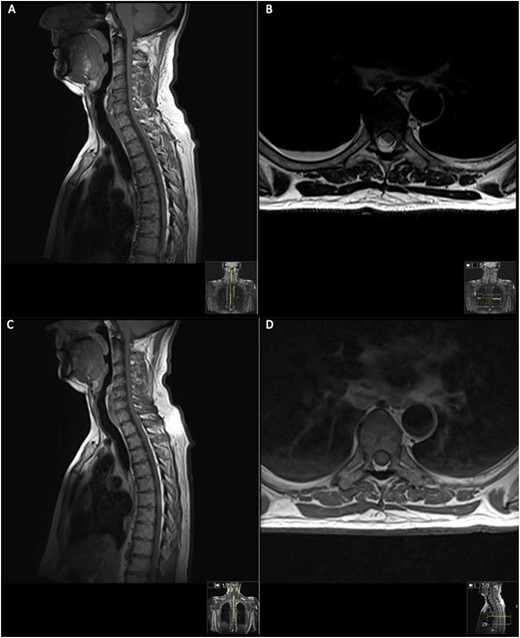

On the second day post-operatively, the patient gained 4/5 power in his hips, knees and right ankle and gained 3/5 power in his left ankle. The patient’s urinary catheter was removed 10 days post-operatively. A post-operative MRI was performed after 19 days showing GTR of the lesion (Fig. 3).

19 days post operative MRI; T1 pre-contrast sagittal (A) and T1 pre-contrast axial (B) show evidence of surgery at T6. Post-contrast T1 sagittal (C) and axial (D) show evidence of a small ‘fleck’ of dural enhancement, however, provide no evidence of any definite residual lesion.